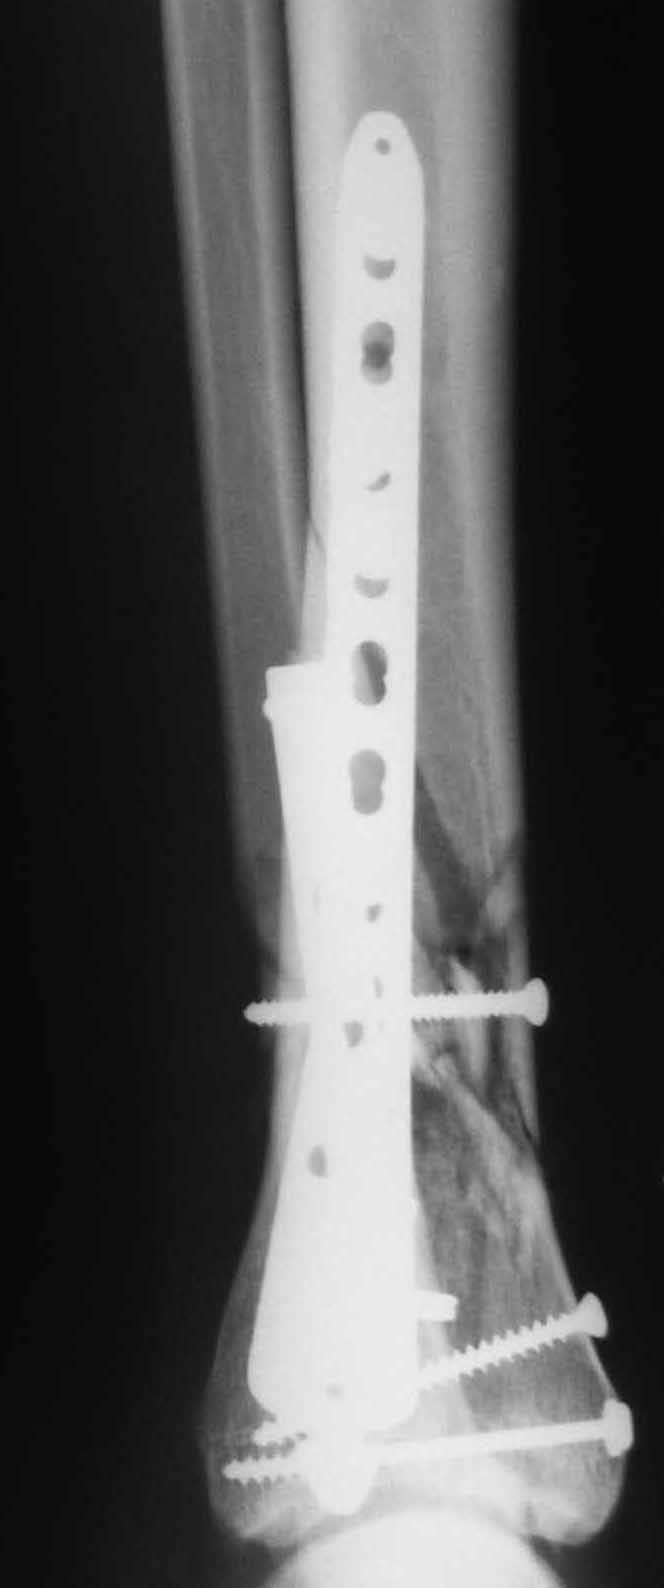

OK, Dr Driagin, Ja operiroval bolnogo po Vashemu, hotia sam ni ochen' ubezden' v itom, t.k. bolnoi otkazalsa na proch' ot ex.fix, ja emu sdelal ORIF + Kostnia plastika, snimky prelogiottsa,

Очень прилично получилось, но мне показалось, что винты на 4,5 мм.Это принципиально винты используются 3,5 и 4,0 мм. И проекцию прямую бы переделать. С уважением Дрягин

На представленном снимке видно, что эпифиз смещен латерально.

Сейчас с этим ничего не сделать, похоже.

Мне кажется, что все конечно далеко от идеала. Сложный перелом. Есть ощущение, что малоберцовая кость (ключ!) фиксирована с ротацией и удлинением. Снимки конечно необходимо сделать в правильных проекциях и без гипса...

Применение шурурпов 4.5 мм и более толстых пластин крайне недопустимы. Рекомендуется низкопрофильные, контурированные пластины с шурупами 3.5 мм, а иногда те же 3.5 шурупы но с головкой 2.7 мм.